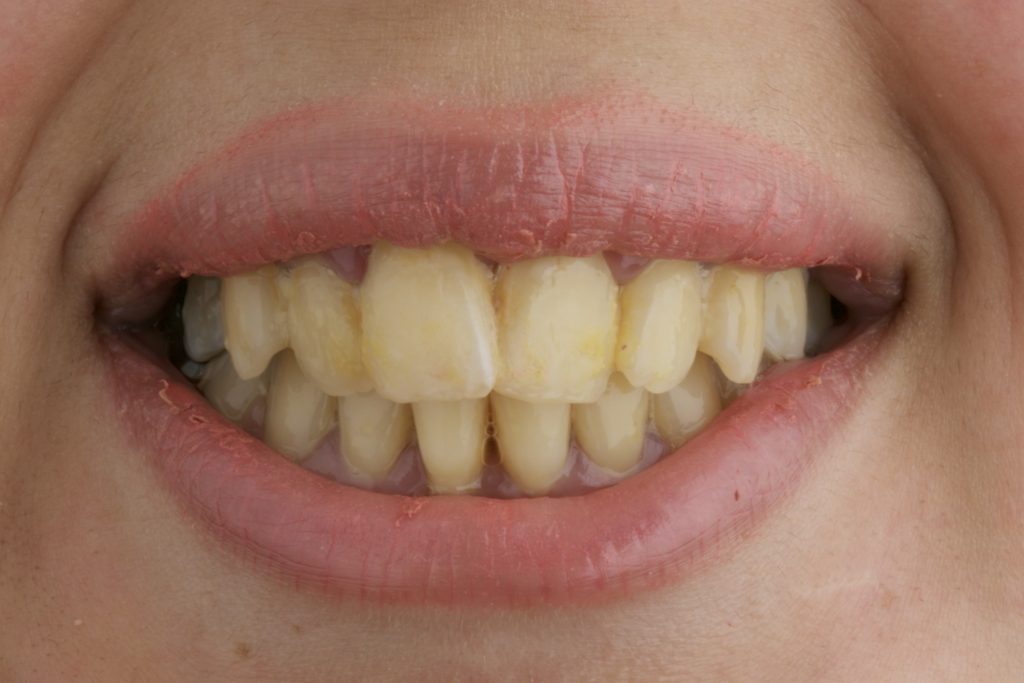

- Shade change achieved from 4M3 to 2R1.5.

- Noticeable esthetic enhancement with a shade improvement of more than two steps on the VITA scale.

- High patient satisfaction with the final outcome.

The shade transition from 4M3 to 2R1.5 highlights the efficacy of the combined protocol used.